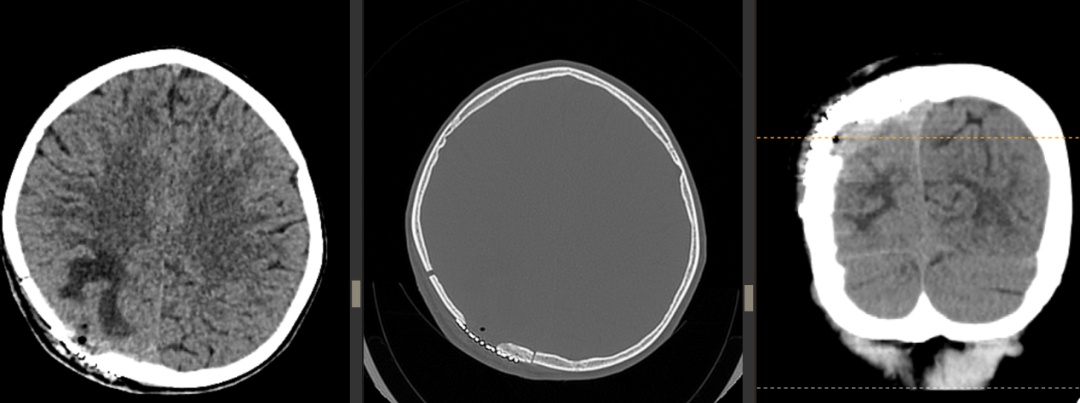

手术历时3个小时,医生成功取出了嵌入脑组织的颅骨碎片、清除血肿,并修复受损的硬脑膜。“手术中我们发现部分颅骨碎片已经刺入脑组织约5毫米,非常接近运动功能区,如果延误治疗可能导致永久性肢体功能障碍。”闫学强回忆道。手术顺利完成,术后癫痫未再发作,小明意识逐渐恢复,语言和肢体活动正常。复查CT显示颅骨形态良好,脑组织无新发出血,小明顺利康复出院。

术后复查CT。